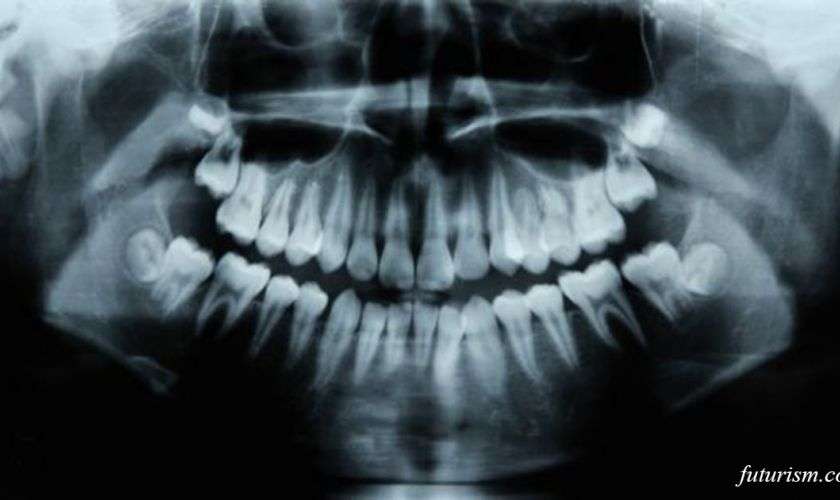

Дентин - это минерализованное вещество под зубной эмалью, которое портится из-за кариеса.

В ходе исследования ученые использовали коллагеновые губки, пропитанные лекарством. Они погрузили их в небольшие полости в дентине зубов мышей. По происшествию шести недель полости практически полностью заполнились новым дентином.